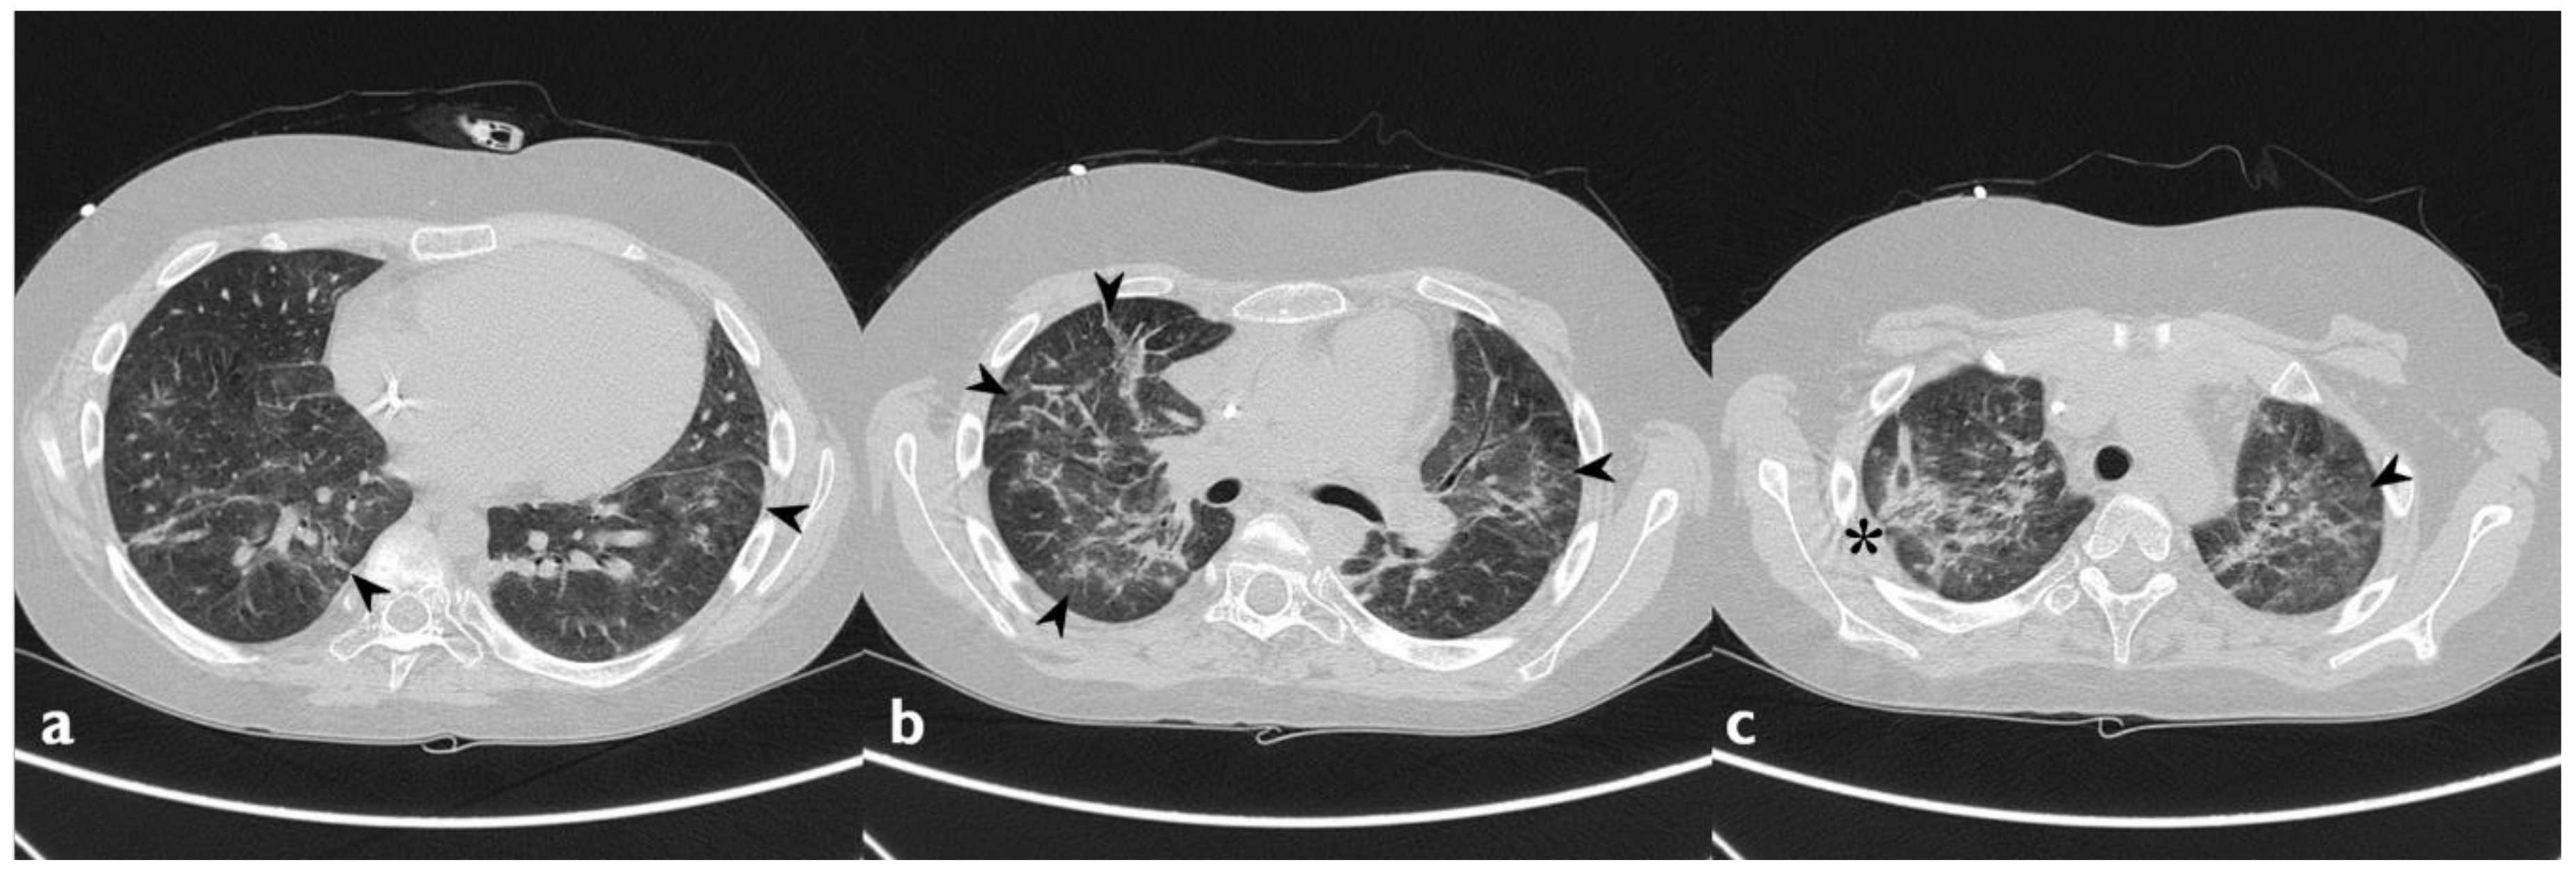

| HRCT Pattern | Associated Drugs |

|---|---|

| Fibrotic pattern | Nitrofurantoin (chronic toxicity), methotrexate, sulfalazina, rituximab, tocilizumab, bleomycin, busulfan, cyclophosphamide (chronic toxicity), amiodarone (form with fibrous course), tocainide, cocaine |

| Organizing pneumonia | Nitrofurantoin (chronic toxicity), methotrexate |

| Mosaic pattern | Nitrofurantoin (acute toxicity), methotrexate, sulfalazina |

| Isolated ground glass | Rituximab, tocilizumab, cyclophosphamide (acute reaction), amiodarone (initial stage), cocaine |

| Alveolar hemorrhage | Penicillamine, rituximab, cocaine |

| Pulmonary edema | Acetyl-salicylic acid, mitomycin |

| Pleural effusion | Sulfonamides, methotrexate |